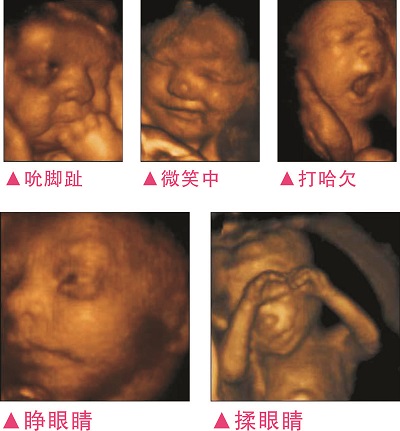

3完整記錄胎兒高清動(dòng)態(tài)寫真

四維容積成像技術(shù),智能光源系統(tǒng)展現(xiàn)梯度亮度,渲染畫面,提高容積成像品質(zhì),高清顯示腹中寶寶的實(shí)時(shí)動(dòng)態(tài)影像,完整記錄寶寶的一舉一動(dòng),讓準(zhǔn)爸媽與寶寶Di一次幸福“見面”,更可刻錄成高清視頻,送給未來寶寶的珍貴禮物。